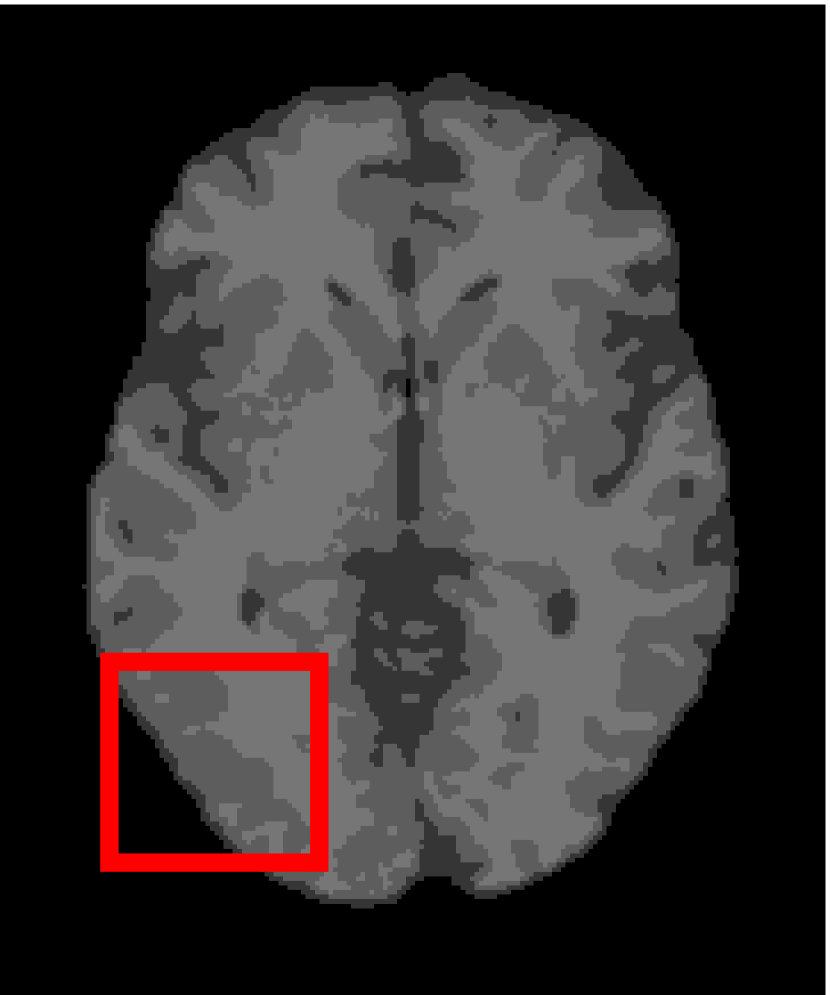

4.4.2 Results on Medical Images

Next, we representatively segment five medical images from BrianWeb. They are represented as five slices in the axial plane with a sequence of 70, 80, 90, 100 and 110, which are generated by T1 modality with slice thickness of 1mm resolution, 9% noise and 20% intensity non-uniformity. Here, we set c=4𝑐4c=4 for all cases. The comparison between WRFCM and its peers are shown in Fig. 9 and Table II. The best values are in bold.

Figure 9: Segmentation results on five medical images. The parameter: ϕ=5.35italic-ϕ5.35\phi=5.35. From top to bottom: noisy images, ground truth, and results of FCM_S1, FCM_S2, FLICM, KWFLICM, FRFCM, WFCM, DSFCM_N, and WRFCM.

By a view of the marked red square in Fig. 9, we find that FCM_S1, FCM_S2, FLICM, KWFLICM and DSFCM_N are vulnerable to noise and intensity non-uniformity. They give rise to the change of topological shapes to some extent. Unlike them, FRFCM and WFCM achieve sufficient noise removal. However, they produce overly smooth contours. Compared with its seven peers, WRFCM can not only suppress noise adequately but also acquire accurate contours. Moreover, it yields the visual result closer to ground truth than its peers. As Table II shows, WRFCM obtains optimal SA, SDS and MCC results for all five medical images. As a conclusion, it outperforms its peers visually and quantitatively.